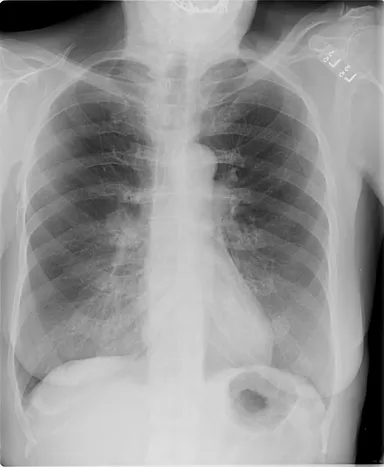

胸部読影支援システム「ClearReadシリーズ」は、先端画像処理技術により胸部X線画像や胸部CT画像の肺野部の視認性を高めることにより、医師が多数の画像を観察してわずかな変化を発見しそれが病気かどうかを判断する読影業務を支援します。あらゆる装置で撮影した画像に対し処理が可能であり、院内の運用を変更することなく、読影補助画像を医師が参照できるようになります。当社が国内で販売開始して以来、「ClearReadシリーズ」は健診施設に限らず一般診療を行う病院でも使用され、導入した施設からは、「読影精度や読影速度が向上した」、「心的ストレスが低減された」などの声が寄せられています。

・胸部X線骨組織透過ソリューション/ClearRead BS※1

胸部X線画像の肋骨や鎖骨などの骨組織を透過した画像を生成し、骨組織と重なり検出が困難であった肺結節や異常陰影などの視認性を向上させる。

・胸部X線経時差分ソリューション/ClearRead +Compare※1

「ClearRead BS」にさらなる画像処理技術を搭載。同一患者の現在と過去の画像から骨組織を透過させるとともにその差分を抽出し、経時的変化部分を強調した画像を生成する。